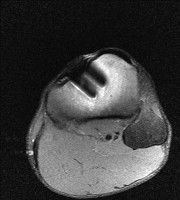

무릎 mri 간단히 봐주실 수 있으시나요 ㅠㅠ

안녕하세요 8년전 십자인대 수술하고 최근 무리한 운동에 무릎 불편감이 생겨서

mri 찍었습니다.

진단결과는 첫 찍은 병원에서 활액막염 이라는 진단을 받았습니다. 혹시 봐주실 수 있으실까요?

올라온 MRI가 단편적이라서 정확한 진단에 어려움이 있지만 십자인대에는 큰 이상이 있지는 않은것 같으며, 무릎관절내 물이 있는 것으로 보아 활액막염의 진단이 맞을 것 같습니다.

하지만 단편적인 영상이기 때문에 촬영병원에서 정확한 판독지 등을 받으시는 것이 좋겠습니다.